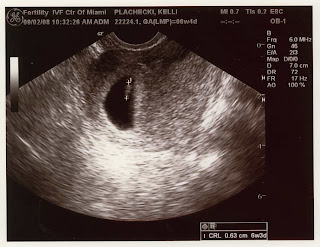

6 weeks pregnant ultrasound. What Causes Bleeding at 6 Weeks Pregnant?. You are 6 Weeks and 1 Day Pregnant. No yolk sac at 6 weeks of gestation may mean either that the pregnancy is less than 6 weeks along or there has been a miscarriage.

Saima Aftab, medical director of the Fetal Care. 6 week transvaginal ultrasound An ultrasound during early pregnancy is usually a transvaginal ultrasound. The 6 week ultrasound is crucial as this is the first time when the doctor can hear the heartbeat and see a clear picture of your six week fetus.

An embryo is usually seen within the gestational sac by 6 weeks gestation. It grows at a rate of about 1 mm a day, starting at the 6th week of gestational age. Your Symptoms Spotting It's not unusual to see some spotting at six weeks, but it should be light, not even enough to cover a small.

At an ultrasound scan at 6 full weeks, a sonographer will most likely be able to spot any type of twin pregnancy. By pregnancy week 6, an ultrasound can reveal how many babies you will carry. The wand will not be painful, although you will feel some pressure and maybe some mild discomfort.

At the 6th week of pregnancy an ultrasound can confirm a pregnancy in all women, the uterus is enlarged, the heartbeat is well heard and seen, the size of a fetus is approximately 4 mm and the fertilized egg is up to 25 mm. Week 6 Fetal. On-screen, it will probably just look like a glowing little blob (but, hey, that’s your beautiful little blob!).

While your healthcare provider counts these two weeks toward your due date, you aren't really pregnant. Week 6 Ultrasound In this 3D image of the developing embryo, you can see a big change since previous week of the first trimester. Approximately six weeks after a pregnant woman’s last period, we can see a small fetal pole, one of the first stages of growth for an embryo, which develops alongside the yolk sac.

4 weeks) Between 5 ½ to 6 ½ weeks, a fetal pole or even a fetal heartbeat may be detected by vaginal ultrasound. You are 6 Weeks and 6 Days Pregnant. Many pregnant women find that moodiness flares up around 6 to 10 weeks.